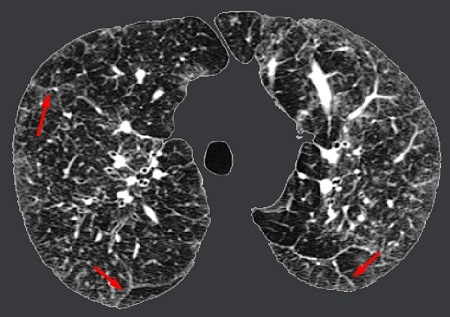

| Một trường hợp bệnh nhân viêm phổi phải thở oxy tại khoa Hô hấp - Ảnh: BV cung cấp |